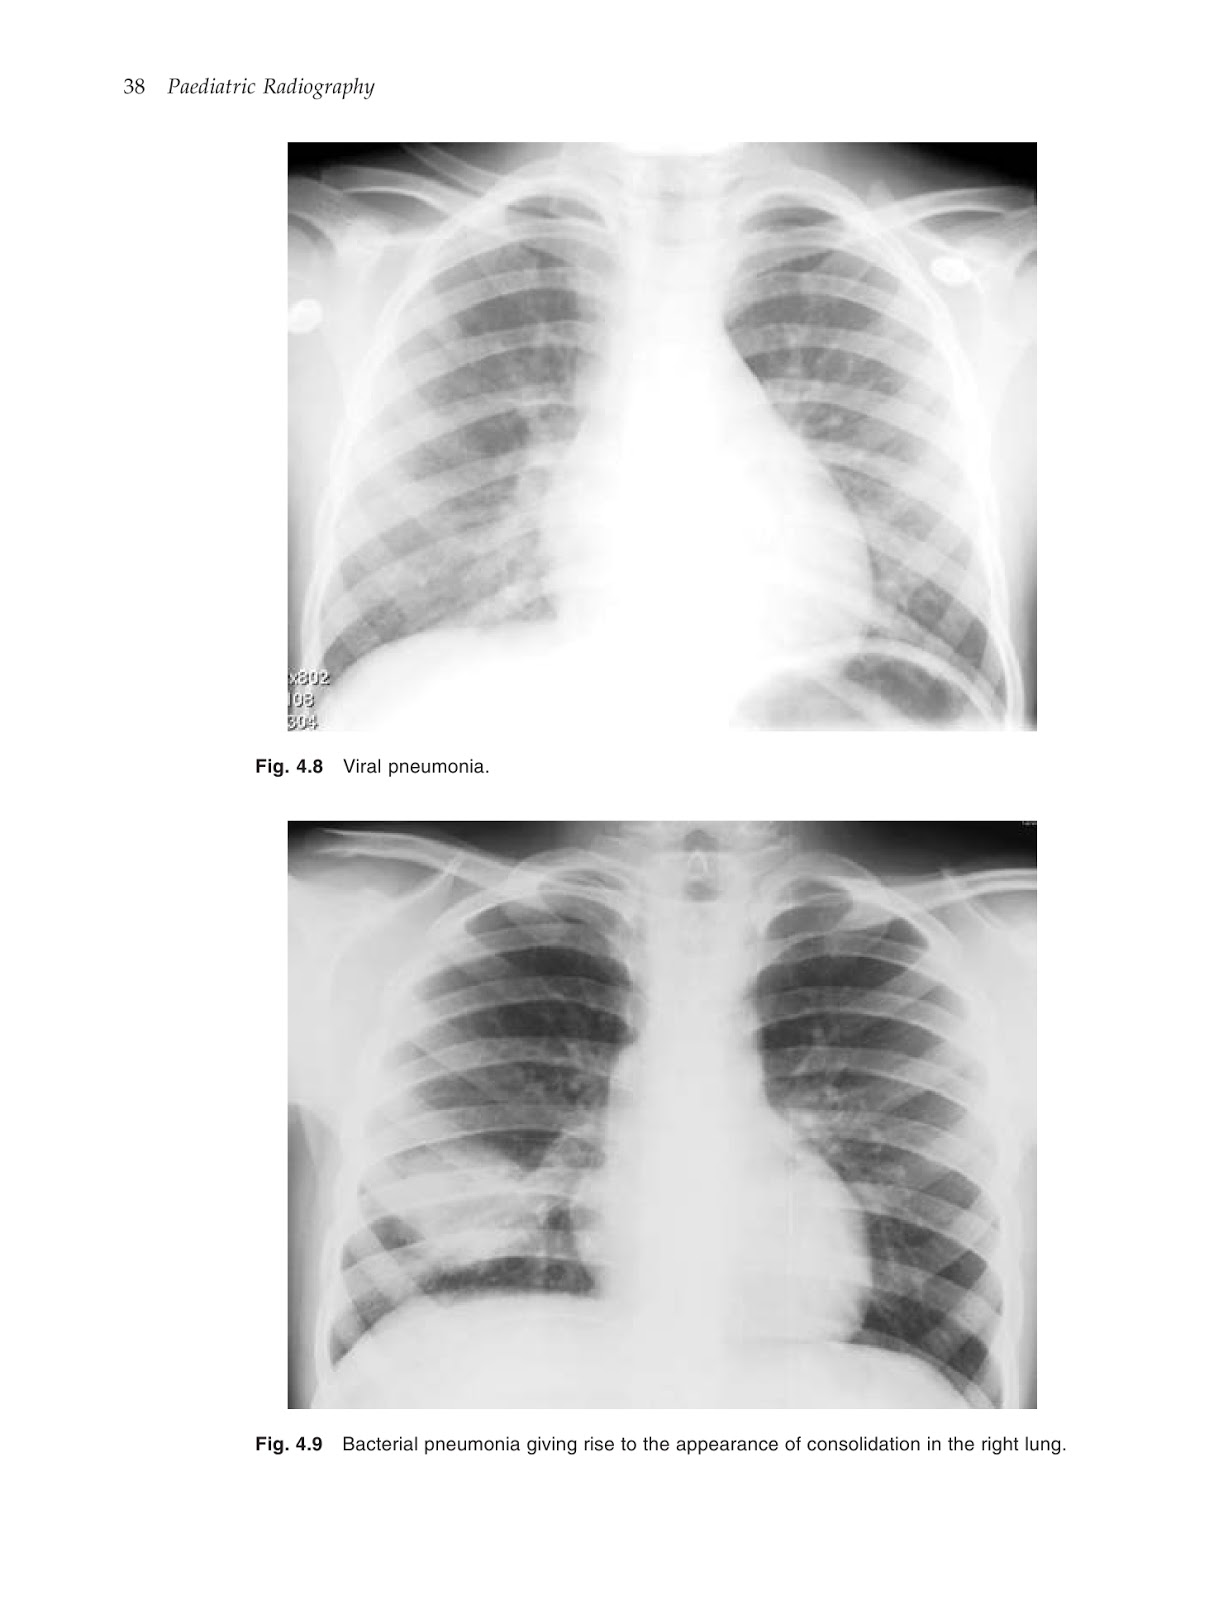

*التصوير الإشعاعي للأطفال (paediatric radiography) بواسطة MARYANN&STEPHEN BOYNES

التصوير الإشعاعي للأطفال (paediatric radiography) بواسطة MARYANN&STEPHEN BOYNES